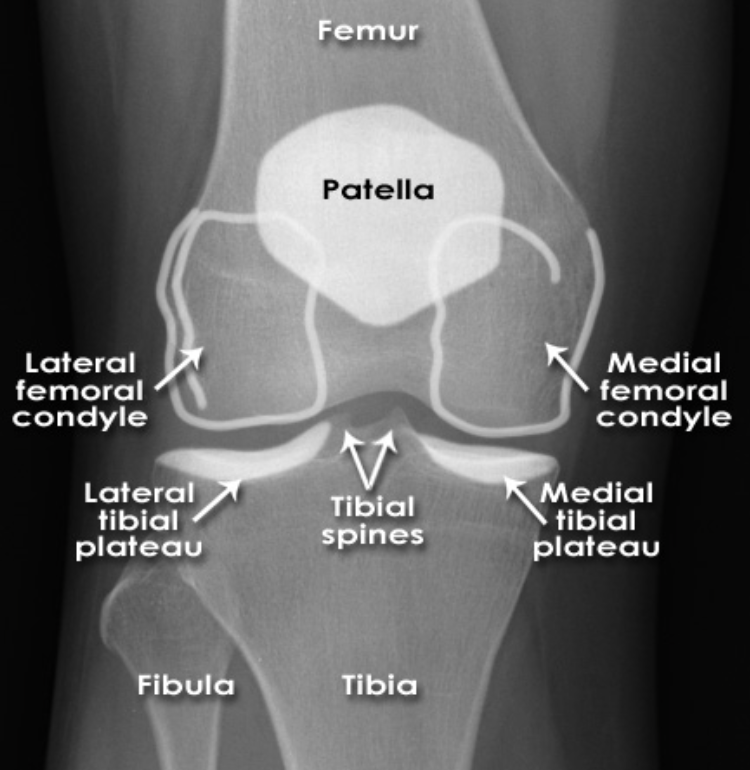

Describe the anatomical components to the knee joint [+]

A